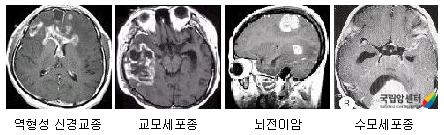

뇌종양의 종류

• 둘째, 악성도에 따라서 구분하면 악성 뇌종양(악성 신경교종, 뇌전이암)과 양성 뇌종양(뇌수막종, 청신경초종, 뇌하수체종양, 양성 신경교종 등)으로 나눌 수 있습니다.

그 중에서 흔한 원발성 뇌종양으로는 신경교종이 40% 정도로 가장 많고, 수막종이 20%, 뇌하수체선종이 15%, 신경초종이 15%, 기타 종양 10% 정도 입니다.